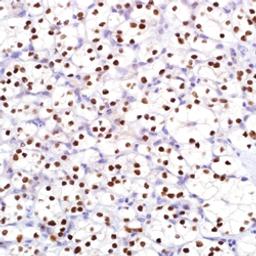

PAX-8 (MRQ-50)

PAX-8 (MRQ-50) Mouse Monoclonal Antibody

PAX-8 is a transcription factor expressed during embryonic development of Müllerian organs, kidney, and thyroid, with continued expression in some epithelial cell types of these mature tissues. It can be useful for marking several types of carcinoma including ovarian serous carcinoma, clear cell renal cell carcinoma, and papillary thyroid carcinoma. Additionally, PAX-8 is not found in the epithelial cells of the breast, lung, mesothelium, stomach, colon, pancreas and other sites.